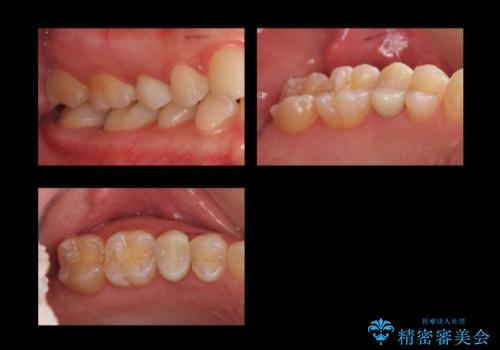

角化歯肉の幅がしっかり合ったため、歯肉をずらすAPF(アピカリ)でなく、切除療法を行いました。

骨外科の量は多かったですが、術直後見られた動揺も治っています。

術後の痛みへの対処は、鎮痛薬を服用していただきます。